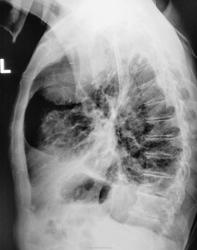

в фазе уплотнения с двух сторон. Справа, судя по размеру, туберкулома, отошедшая в мир иной.

Игорь Артурович!Т.е. туберкулома опорожнилась и сьежилась,скукожилась ???А вправом корне-россыпь кальцинатов.

в ПТД, так у больного имеется вспышка туберкулезного процесса. См. рисунок. Стрелки указывают активные очаги. С уважением Nikolas

Но, прошло полтора года, и гражданина с "флюшки" опять "зацепили" и провели дообследование.

Снимки выставлены в хронологическом порядке. Первая серия 2009 год, вторая серия - через полтора года. Последние снимки от "вчера".